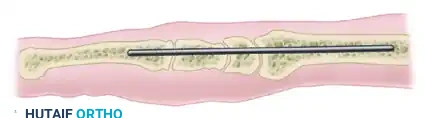

Once the wrist is reduced into the optimal position (neutral flexion, slight ulnar deviation), rigid fixation is achieved using heavy Steinmann pins.

- Transfix the carpus with two stout Steinmann pins measuring 7/64 to 9/64 of an inch in diameter.

- The pins are typically driven in a retrograde fashion. Introduce the pins through the dorsal aspect of the second and third metacarpals, driving them proximally across the prepared carpal mass and seating them deeply into the medullary canal of the distal radius.

FIGURE 72-10 (A): Lateral schematic demonstrating the longitudinal trajectory of the Steinmann pin traversing the metacarpal, the remaining carpus, and seating securely within the medullary canal of the radius.

- Ensure the pins cross the fusion sites at divergent angles to maximize rotational stability.